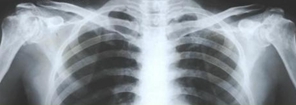

摘要:學好醫(yī)學基礎知識是學好醫(yī)學影像學的保證。現(xiàn)代影像診斷是通過人體組織器官異常密度、回聲、頻譜及信號變化來反映病變存在的,這些不同的影像特征代表著疾病的病理演變過程。

學好醫(yī)學基礎知識是學好醫(yī)學影像學的保證?,F(xiàn)代影像診斷是通過人體組織器官異常密度、回聲、頻譜及信號變化來反映病變存在的,這些不同的影像特征代表著疾病的病理演變過程。只有學好相關的基礎課程,才有可能學好醫(yī)學影像學。應學好化學、物理學、電子計算機等學科。有助于理解醫(yī)學影像設備的成像原理,正確使用各種檢查器械。應熟悉大體解剖和斷面解剖。有助于正確認識影像解剖鑒別正常、異常和變異,才能對病變部位準確的認識、定位和描述。應掌握病理解剖學和病理生理學。將病理基礎與醫(yī)學影像征象有機聯(lián)系將大大有助于對所見影像征象的理解與掌握,并對疾病做出正確診斷。